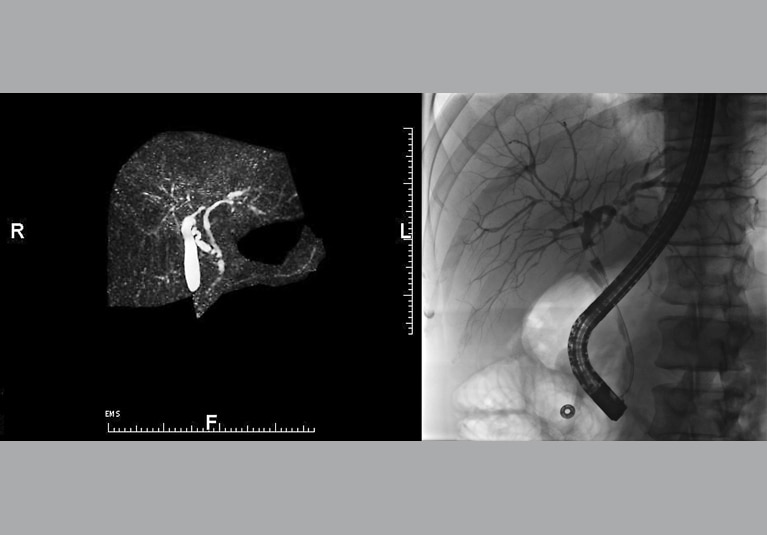

157. Feb. 09, 2019

Advanced imaging and endoscopic tools enhance diagnosis and treatment of PSC and cancer surveillance

Mayo specialists employ highly specialized magnetic resonance cholangiopancreatography (MRCP) to diagnose and manage primary sclerosing cholangitis (PSC) in a large cohort of patients.